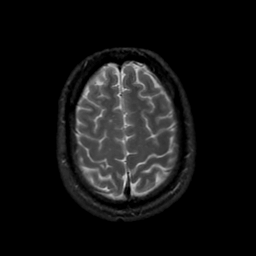

MR Study #22, December 1, 1991 -- Slice #41

[Home][Help][Clinical][Tour 1][Tour 2] Slice 41